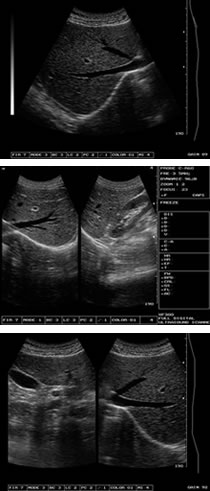

XF-300B型超聲診斷儀